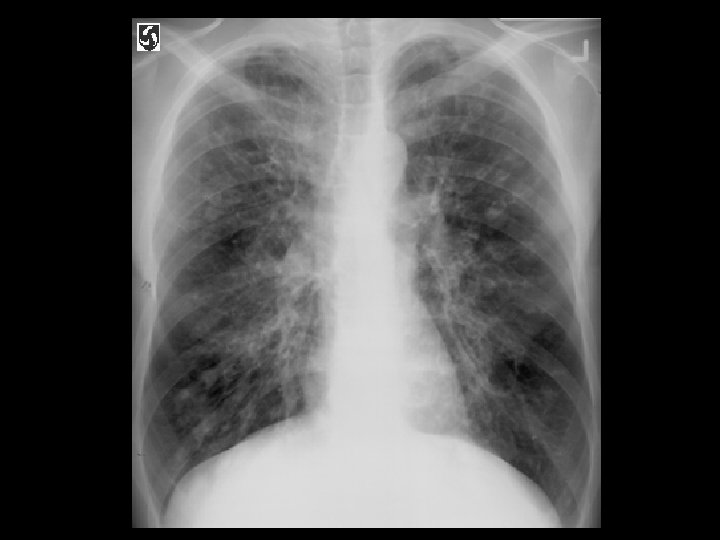

Tuberculosis • Findings: – patchy parenchymal opacities – focal bronchiectasis and accompanying bronchioliltis – bilateral distribution • ddx: – endobronchial spread of tumor